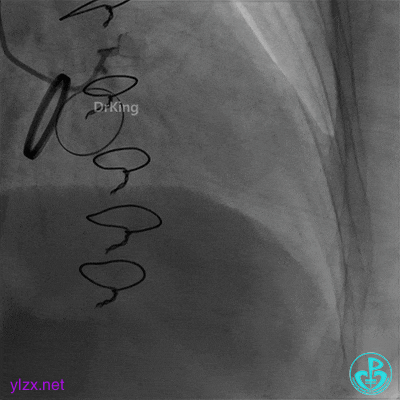

06 治疗过程

经指引导管冠脉内推注尿激酶原20mg后造影(抽吸导管及延长导管已用完),下台。